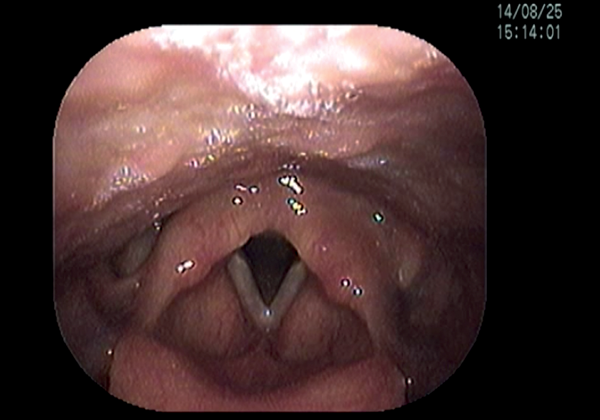

Short-term complications include perforation of the inner perichondrium and asymmetric laryngofissure. In the long-term, implant infection is rare. Hoarse voice or breathy voice can occur as well as recurrence of symptoms in about 10 % of cases. Revision surgery is rare. If it is required, this is usually due to breathy voice from a too wide titanium bridge. The long-term outcomes of this procedure are good. Figure 19 shows the vocal cords before and after surgery.

Figure 19: top 2 pictures) Before adduction, bottom 2 pictures) after adduction.